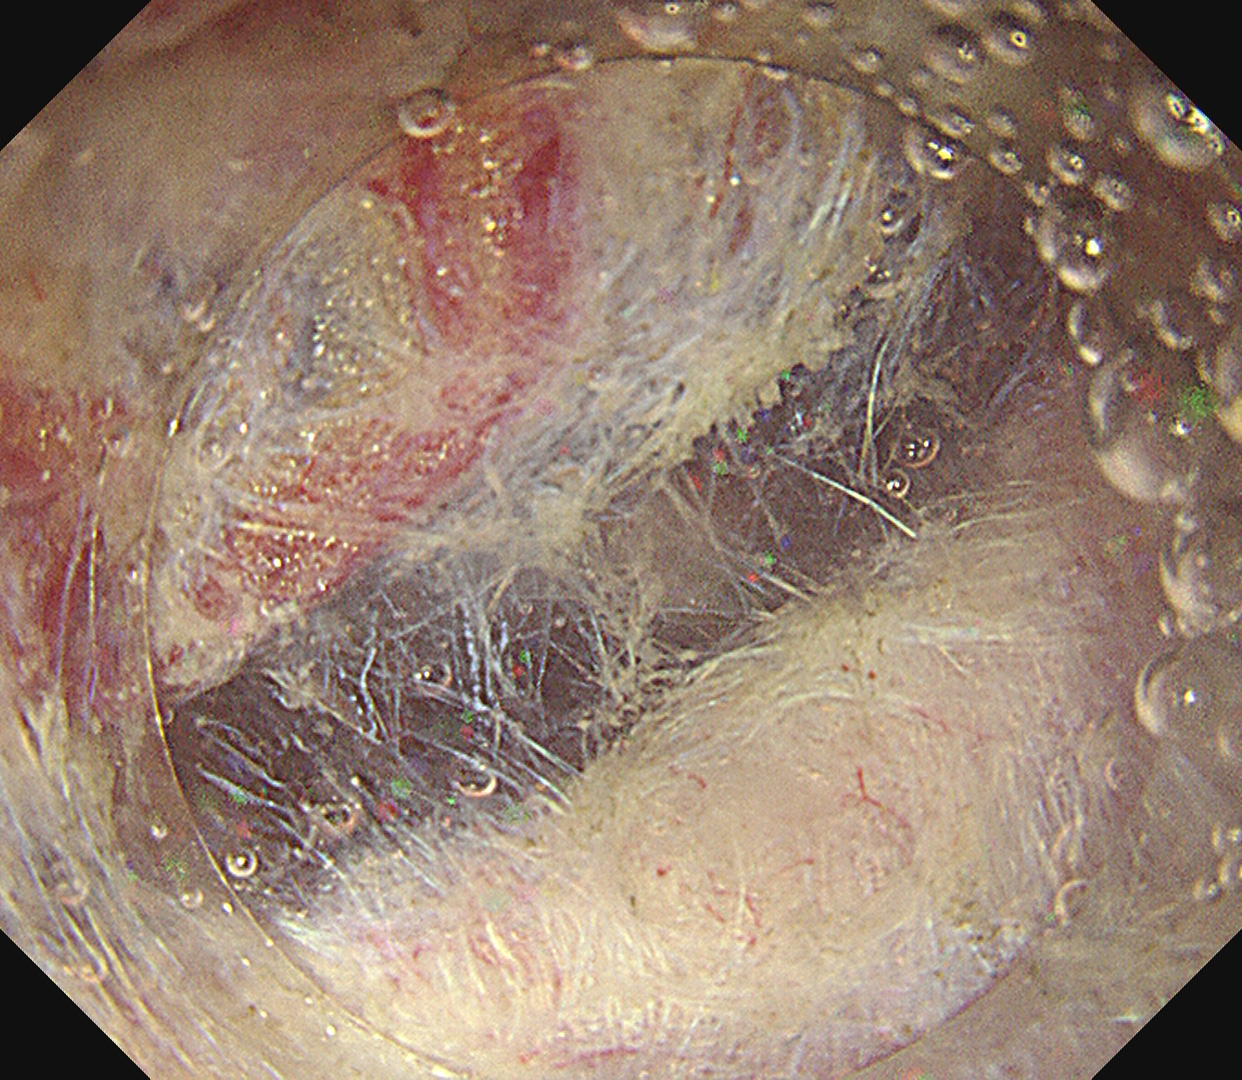

早期胃癌(SM浸潤がん)ESD

- EMR・ESD による早期消化管癌の低侵襲治療